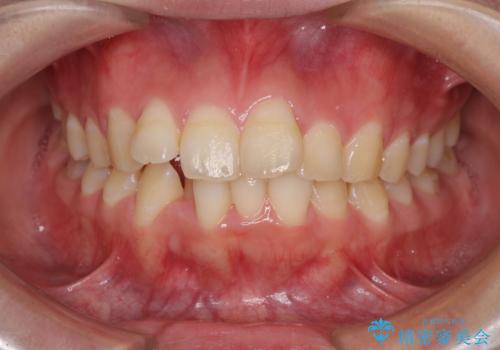

前歯の出っ歯と口の閉じにくさを抜歯矯正で改善 目立たないワイヤー矯正

出っ歯を改善した後に真っ白な歯に 矯正歯科治療と審美歯科治療